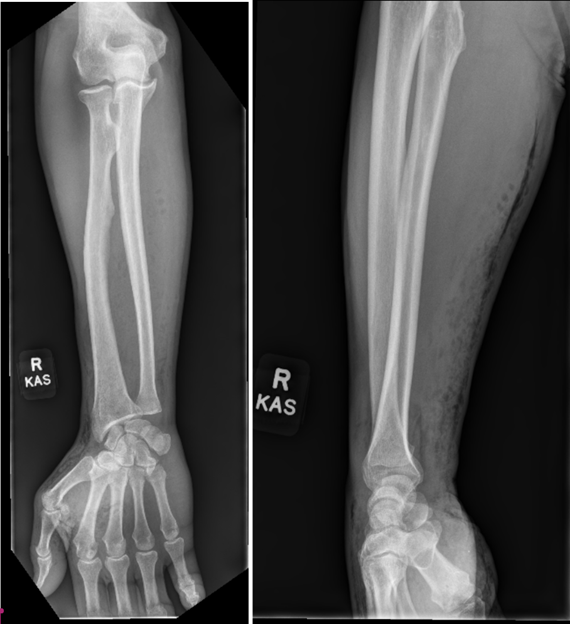

Subcutaneous emphysema (SE) involves the presence of air or gas within the subcutaneous tissue [1]. It can result from various sources, including surgical procedures, trauma, infections, or spontaneous events [1,2]. While SE in the hand and upper extremities following minor trauma is rare, it has been reported in a few clinical cases [1,3,4,5,6,7,8,9]. Healthy patients with minor trauma-induced SE, as presented in this case, typically do not warrant intensive or surgical treatment. Most patients with uncomplicated traumatic SE can be effectively managed with conservative treatment, including proper wound care and antibiotics [1,10]. This approach is recommended for patients who are systemically stable, have minimal pain, and show no signs of extensive cellulitis [9,11]. However, consideration for necrotizing fasciitis (NF) must be made through a thorough review of the patient’s history, clinical examination, and evaluation of the Laboratory Risk Indicator for Necrotizing Fasciitis (LRINEC) score, clinicians can guide management appropriately and prevent unwarranted surgical intervention in a high-stakes diagnosis [1,12]. The LRINEC score, developed by Wong et al. in 2004, uses six laboratory values – C-reactive protein (CRP), total white blood cell (WBC) count, hemoglobin (Hgb), sodium, creatinine, and glucose – to stratify patients into low, medium, or high risk for NF [12,13]. A score of 6 or more is concerning, while a score above 8 is highly predictive of the disease [1]. Distinguishing SE from more severe conditions, such as NF, is critical due to the rapid progression and potential for extensive damage involving the skin, fascia, subcutaneous tissues, and muscle [1]. This condition is frequently associated with an external injury that introduces skin or environmental pathogens into the deeper soft tissue layers [14]. The presence of acute swelling with crepitus on physical examination and subcutaneous gas seen on radiographs suggests a necrotizing soft tissue infection (Fig. 1) [14,15]. The incidence of NF is estimated to range from 0.3 to 15 cases/100,000 people [16].

Figure 1: Anteroposterior and lateral of the right forearm radiographs revealing soft tissue gas from the first and second webspace going proximal up the volar and lateral forearm.